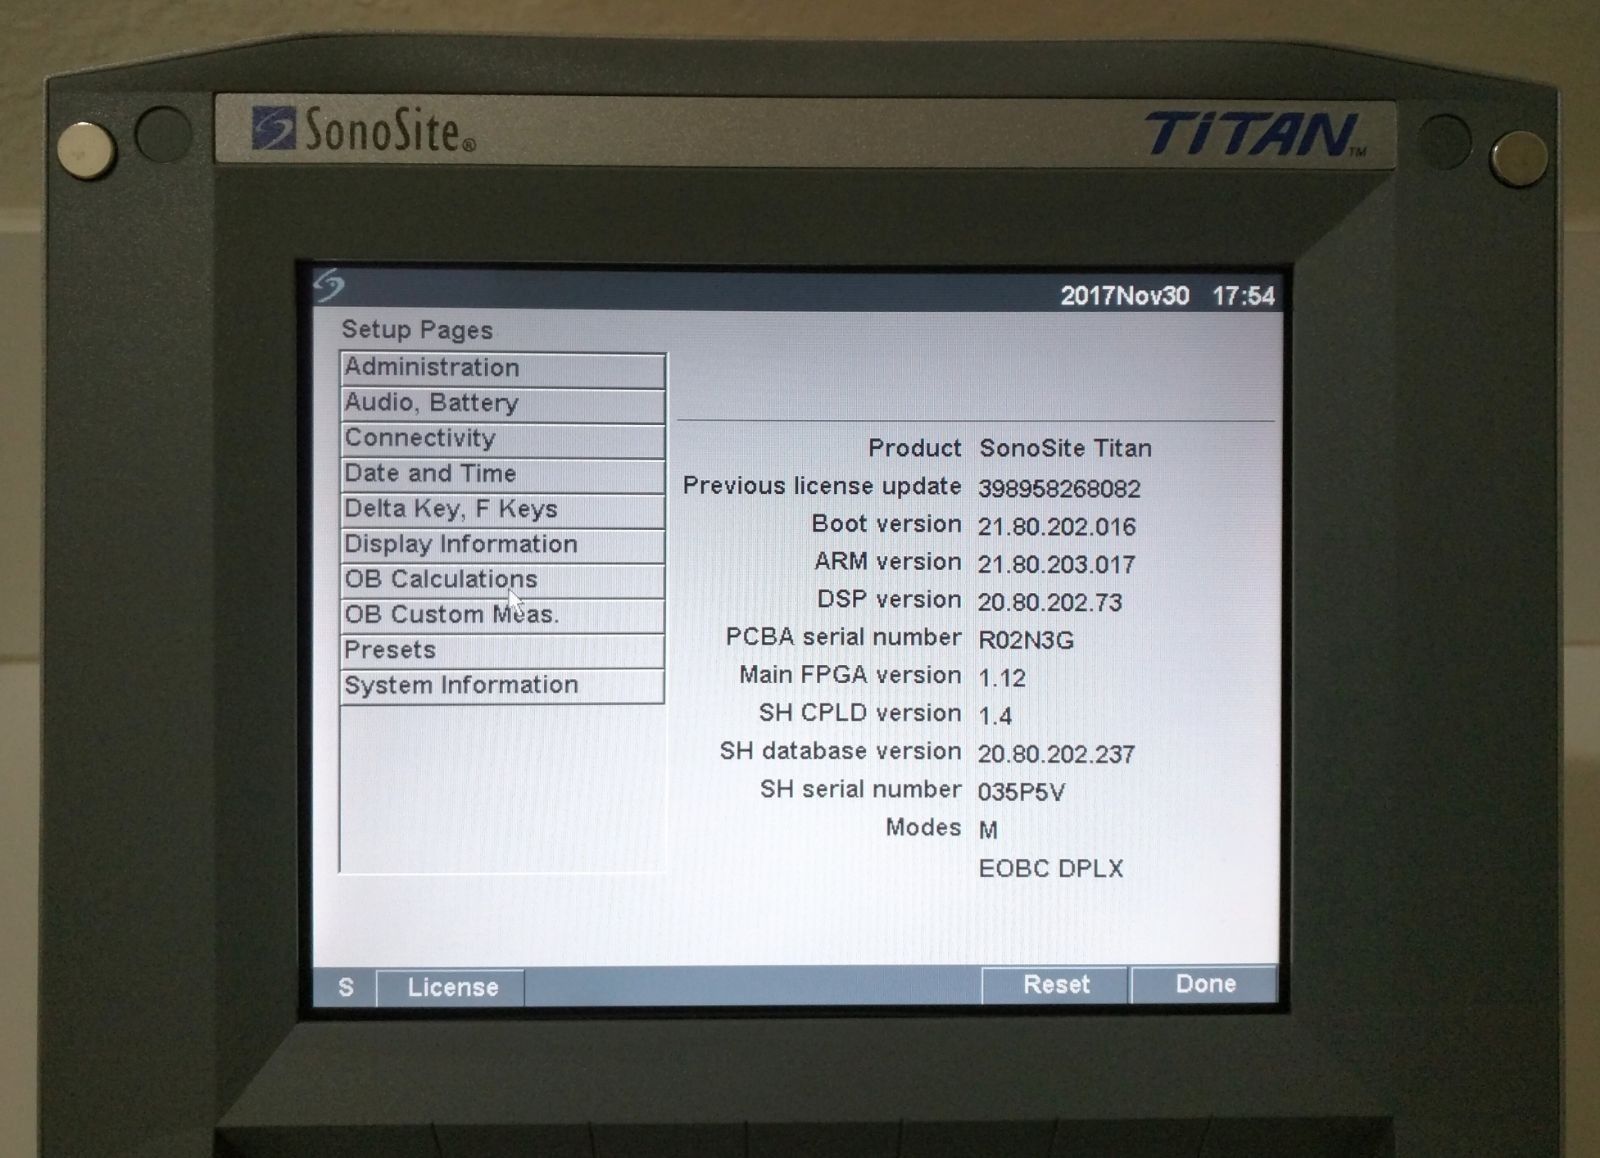

The SONOSITE TITAN is built for durability, capable of withstanding the demands of a busy clinical environment. Its robust construction ensures reliability, meaning that healthcare providers can trust it during high-pressure situations. Furthermore, regular updates to its software keep it at the forefront of medical imaging technology, ensuring continuous improvement and long-term satisfaction for all users.